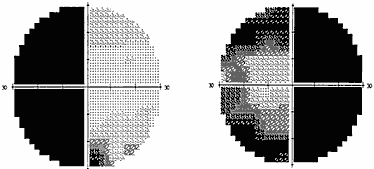

В силу различных причин, в частности, из–за строения диафрагмы турецкого седла, опухоль может распространяться не столько кверху, сколько латерально, в сторону кавернозного синуса – латероселлярный рост. Зрительные нарушения, которые присутствуют при этом росте опухоли, чаще представлены асимметричным хиазмальным синдромом со значительным, вплоть до практической слепоты, понижением остроты зрения на одном глазу. Может также развиться одноименная (односторонняя) гомонимная гемианопсия (рис. 2) в результате воздействия опухоли на зрительный тракт. Дефекты поля зрения появляются в половине поля зрения на стороне, противоположной локализации опухоли. Офтальмологи должны быть внимательны, поскольку дефекты поля зрения при латероселлярном росте опухоли и развитии асимметричного хиазмального синдрома или гомонимной трактусной гемианопсии появляются в носовой половине поля зрения на глазу на стороне преимущественного роста опухоли (рис. 3). Это может спровоцировать ошибочную диагностику глаукомы.

Рис. 2. Полная правосторонняя гомонимная гемианопсия (автоматическая статическая периметрия)

Рис. 3. Начальная левосторонняя гомонимная гемианопсия (автоматическая статическая периметрия)